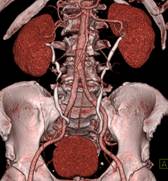

320排螺旋CT具备16cm宽覆盖探测器,实现动态容积扫描,360度的各向同性采集能力及[email protected]%密度分辨率的量子探测器,一次心跳全心脏采集,一圈扫描器官成像,一次检查完成多重任务,实现真正的动态容积体灌注及心脏、神经一站式检查;西门子Flash炫速CT扫描系统,具备两套同时旋转的X射线球管及探测器,实现了43cm/s的极快CT扫描速度和75 ms的时间分辨率,完成全胸扫描仅需0.6秒,使得患者做心脏扫描时无须食用β-受体阻滞药,亦无须屏气,并可实现低于1mSv的超低辐射剂量,配置第二代双能量、宽151级纯化能谱,组织鉴别能力进一步提高,可开展多达10余种双能量成像应用。

脑血管畸形CTA ,大血管成像:动态容积成像实现大范围动态血管检查